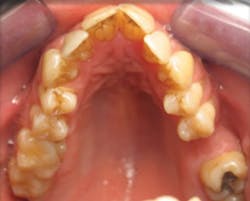

Case 3: 17-year-old male: 1-year treatment. Expanding and proclining delivered more room for the tongue and increased oral cavity volume without IPR or extractions. Case and photos courtesy of Dr. Ben Miraglia.

Before: V- and omega-shaped arch, crossbite. After: U-shaped arch, no IPR, no EXT, increased oral cavity volume.